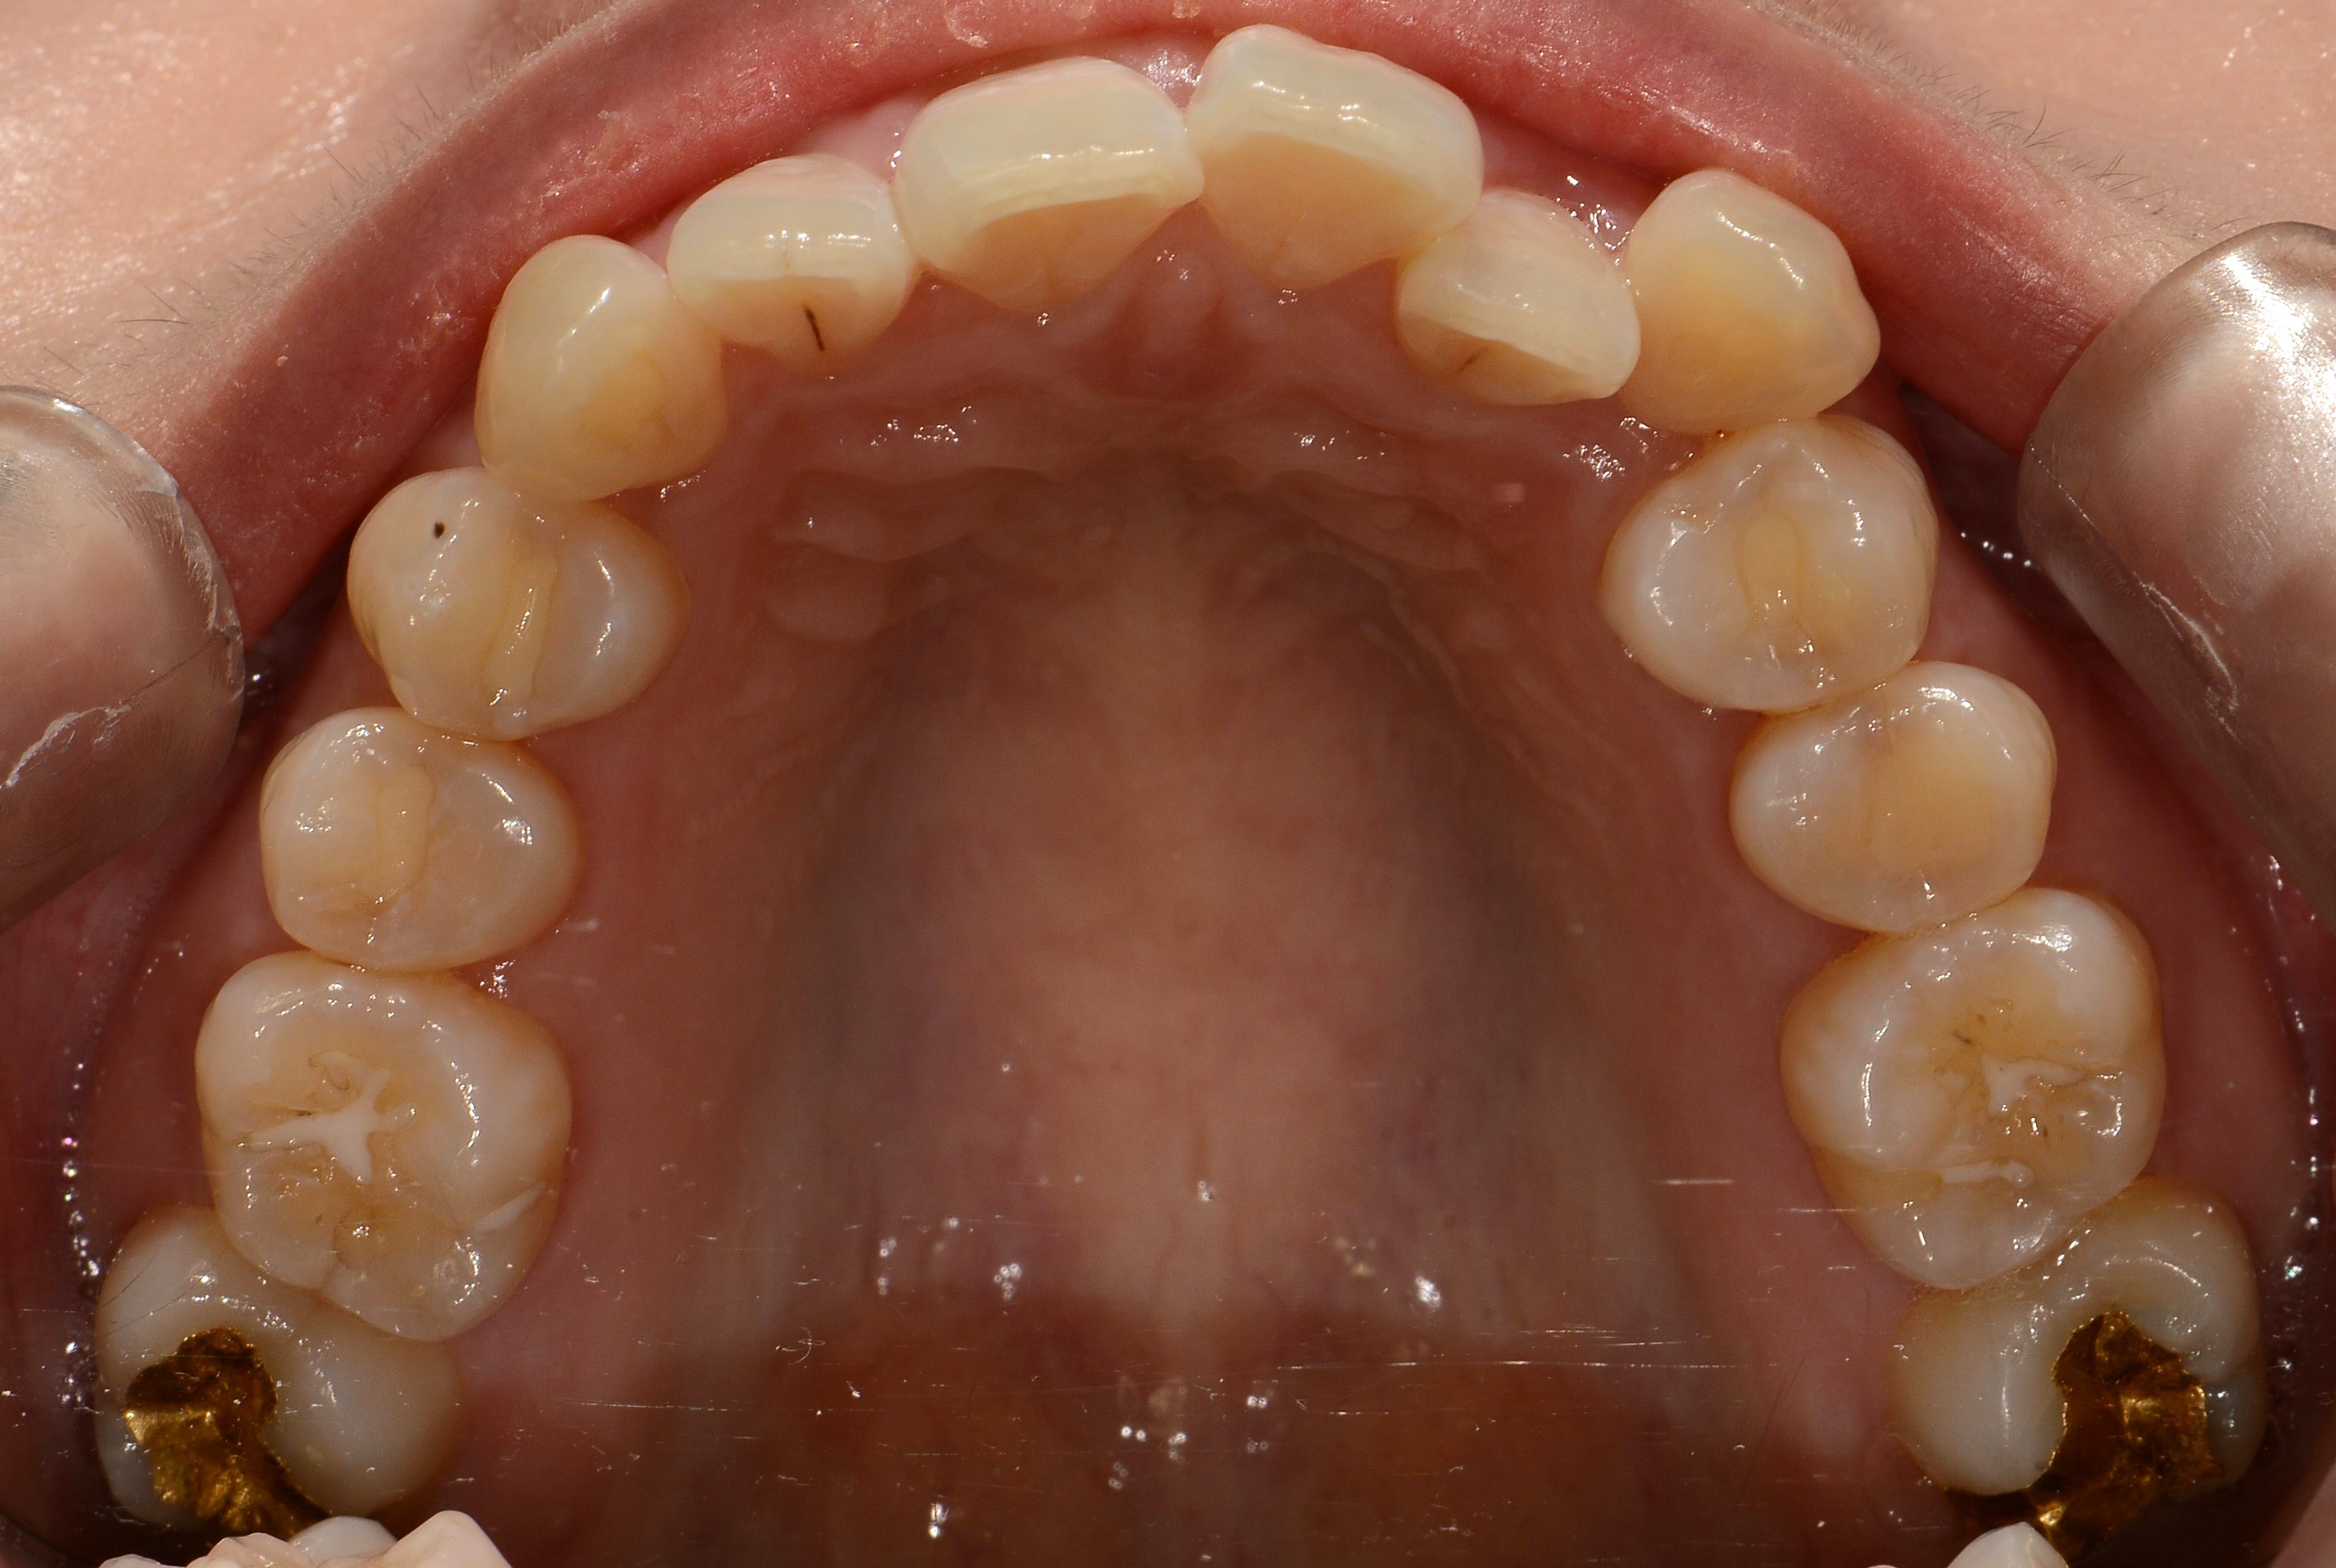

치료 전 사진입니다.